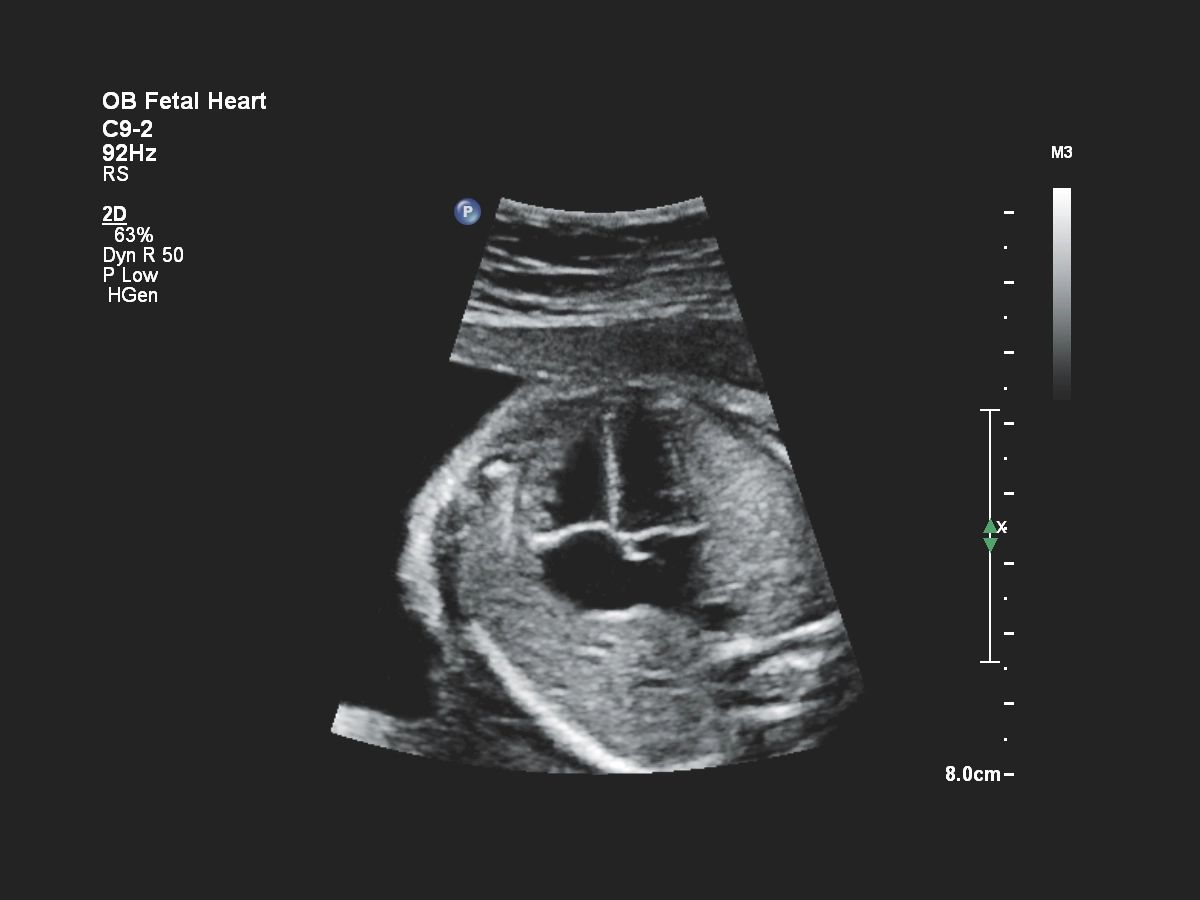

- Акушерство

- Кардиология

Функции для кардио-исследований

- Fetal Heart Navigator - функция для навигации сердца плода

- Навигатор для УЗИ-сердца плода FHN